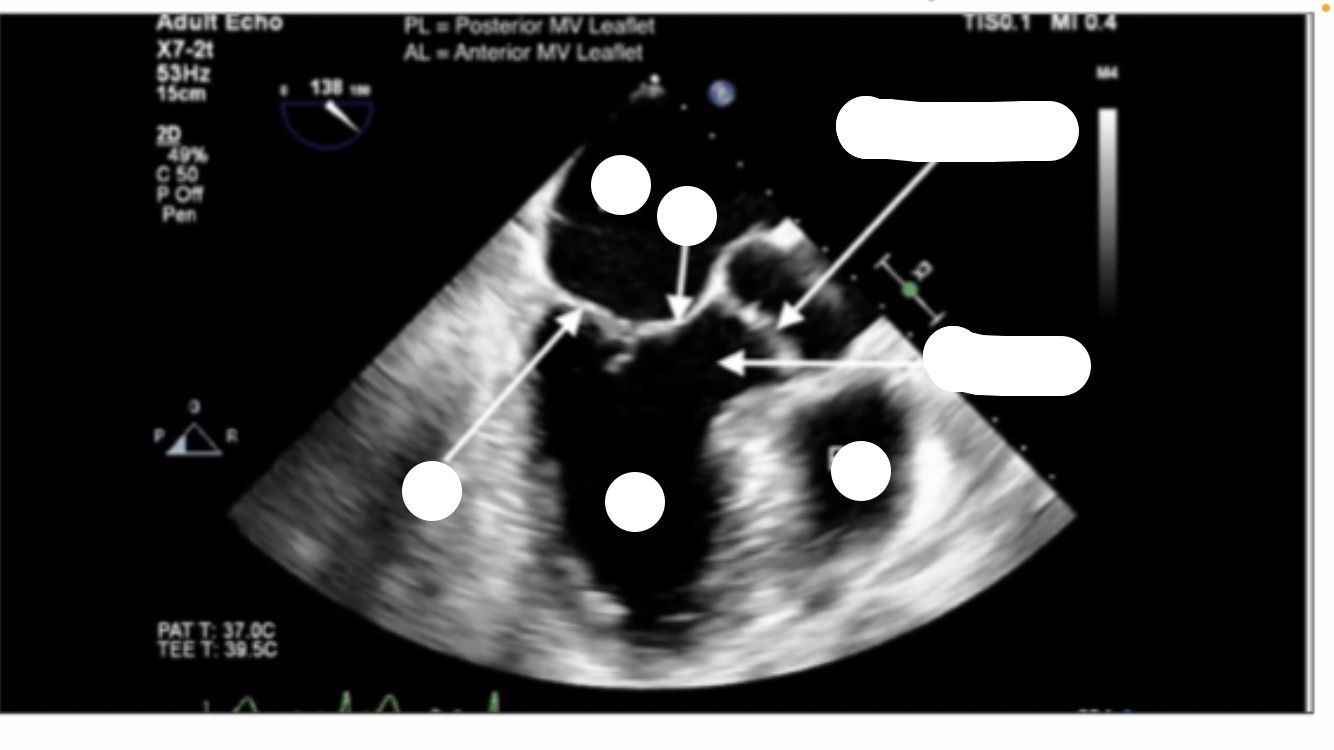

Mid-esophageal Long Axis view. LAX

midesophageal long axis